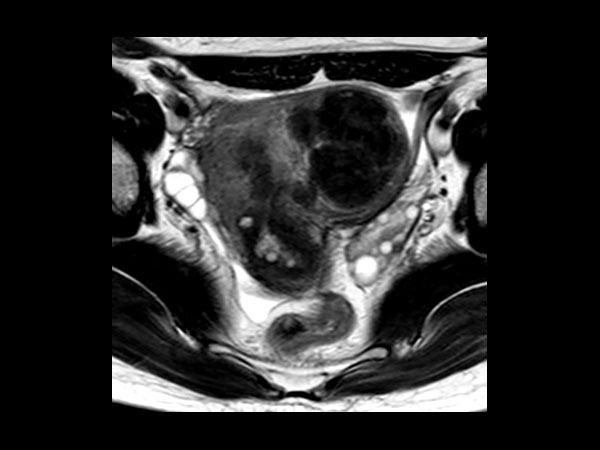

Female Pelvis

Toyonaka Hospital, Japan